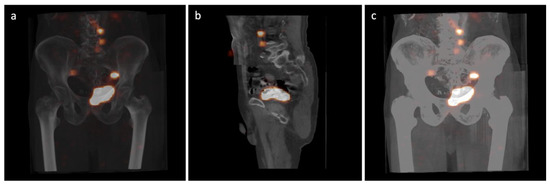

2.2. Radiocolloid Injection and SPECT/CT Imaging

- Połom, W.; Markuszewski, M.; Cytawa, W.; Lass, P.; Matuszewski, M. Radio-Guided Lymph Node Mapping in Bladder Cancer Using SPECT/CT and Intraoperative γ-Probe Methods. Clin. Nucl. Med. 2016, 41, 362–367. [Google Scholar] [CrossRef] [PubMed]

- Sherif, A.; Garske, U.; de la Torre, M.; Thörn, M. Hybrid SPECT-CT: An Additional Technique for Sentinel Node Detection of Patients with Invasive Bladder Cancer. Eur. Urol. 2006, 50, 83–91. [Google Scholar] [CrossRef] [PubMed]